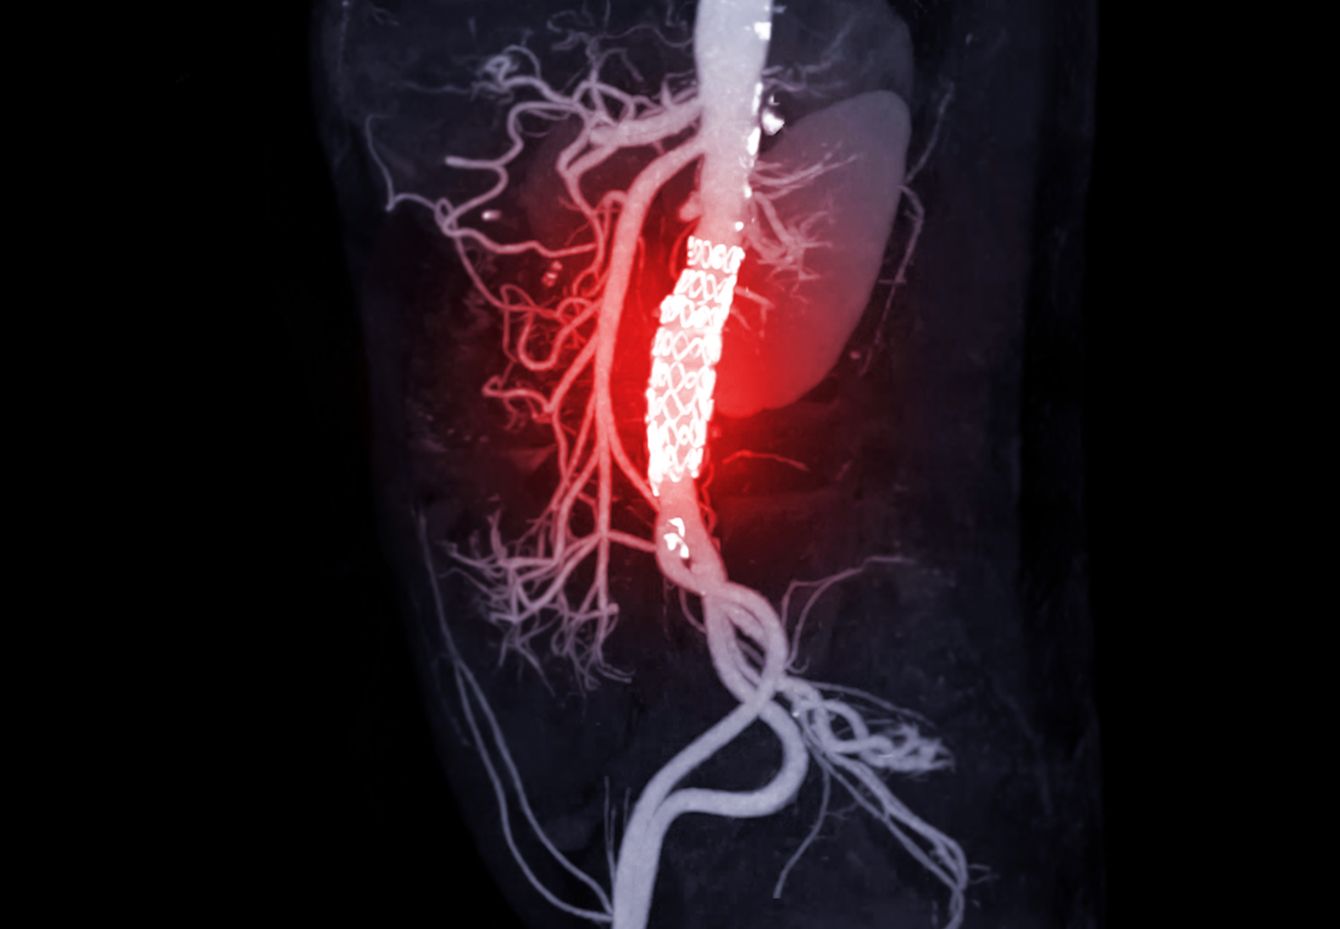

※写真はイメージです